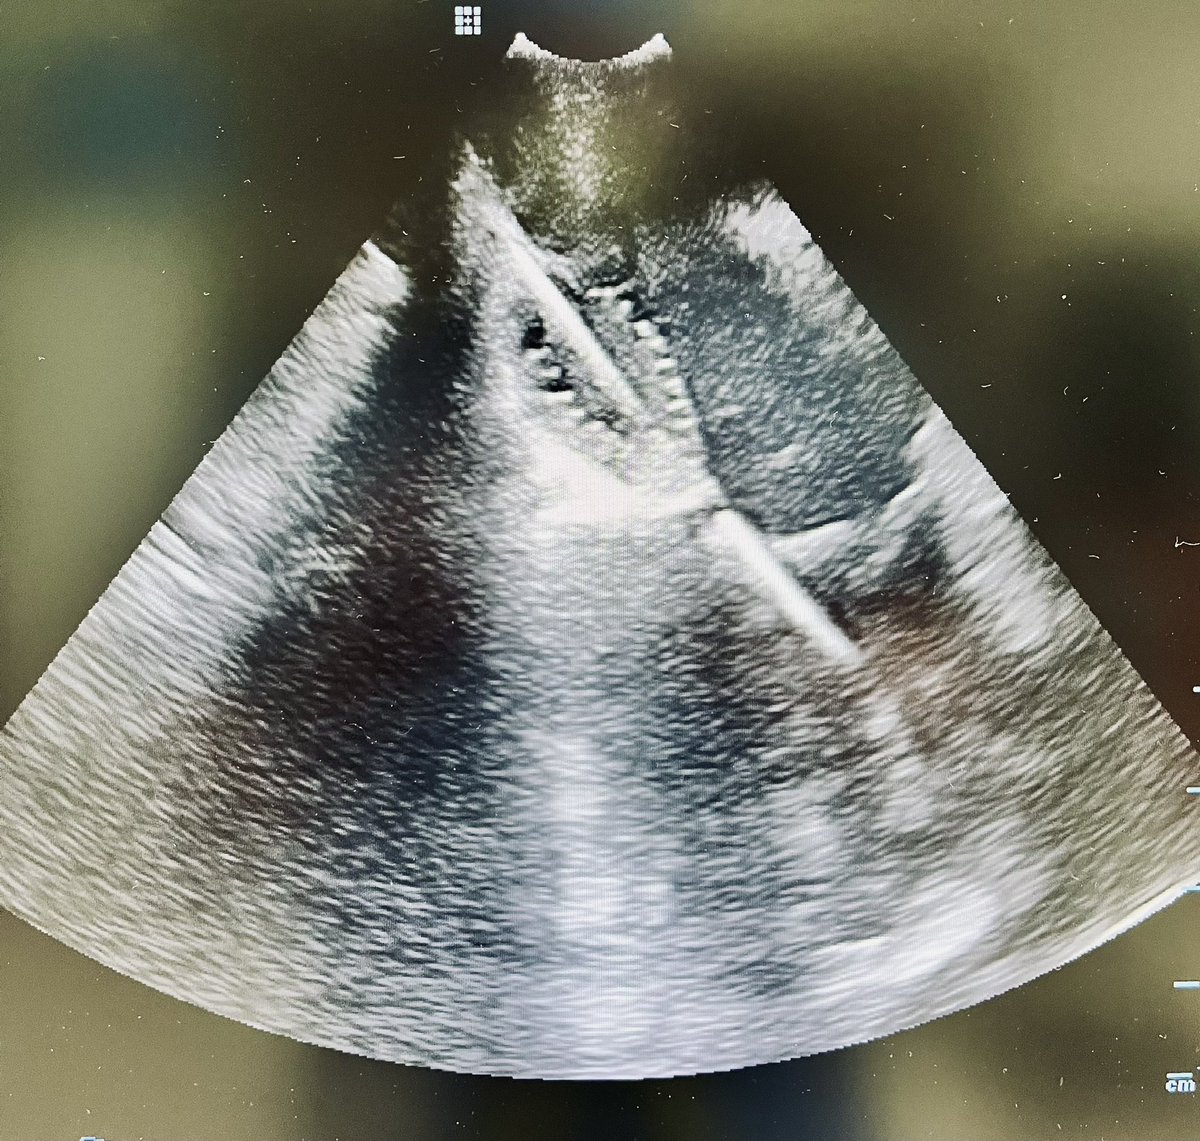

Validation of an Automated Premature Ventricular Contraction Mapping Algorithm